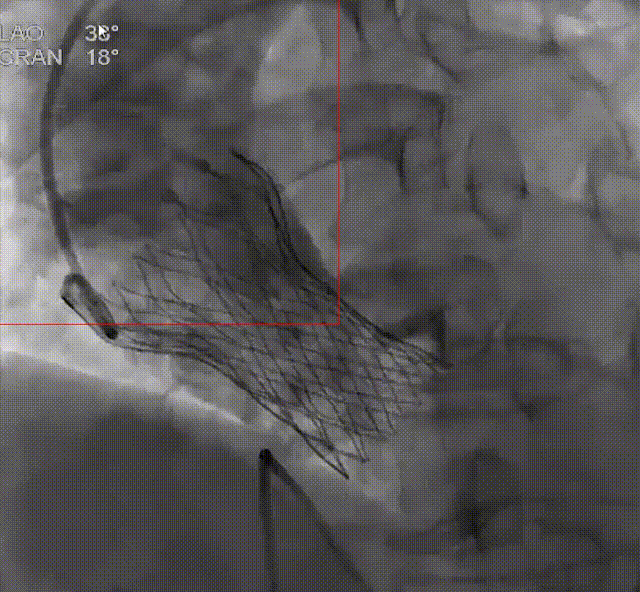

王焱教授展示了厦心医院已完成的5例机器人辅助TAVR手术的临床数据:该组患者平均年龄72.4岁,均为主动脉瓣重度狭窄。术后即刻技术成功率为100%,机器人完成的全部TAVR系统从进入人体到撤出过程,平均时长15分钟。目前5例患者均已完成30天随访,均无主要心脑血管事件的发生,人工瓣膜血流动力学指标符合治疗预期,无延迟的并发症出现。

术后即刻造影

该临床试验结果已初步展示出该系统的稳定性和优异性能。5例病例涵盖了常见的各种解剖类型,包含2例Type 1型二叶瓣,1例Type 0型二叶瓣,2例不同钙化程度的三叶瓣,钙化积分最低的仅92,最高的HU850积分达到了1560,涵盖了不同手术难度和解剖类型的病变。这些持续的临床结果为未来机器人辅助TAVR手术的可行性和安全性提供了坚实的证据。